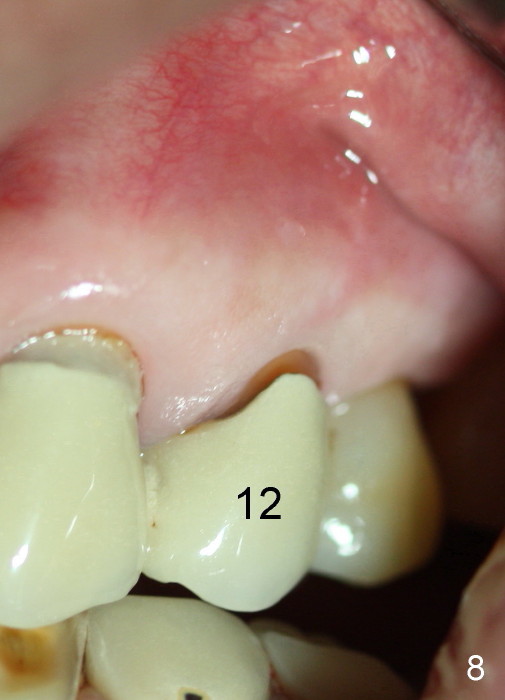

One month later, the fistula is regressing, while the pain reduces (Fig.4). It appears that the initial access is not extended lingually enough (Fig.5). The lingual canal is still non-negotiable when the access is enlarged (Fig.6). Working length of the buccal canal is confirmed with 30/.06 Gutta Percha in place (Fig.7). After explanation and consent, RCT is finished routinely. Two months postop, the buccal apical fistula resolves with no symptom (Fig.8). The retainer at the site of #12 is not removed to increase chance of finding the missing canal. It is part of a long bridge.